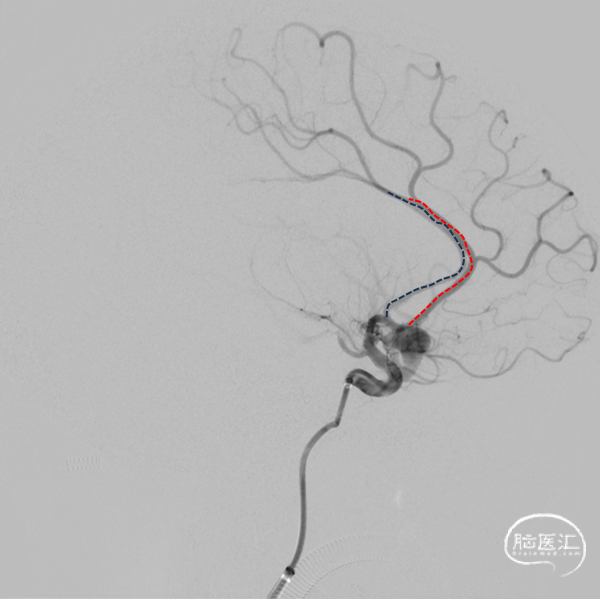

题目:左侧大脑中动脉M1段夹层动脉瘤FD植入术

Title:Flow Diverter (FD) implantation for a dissecting aneurysm at the M1 segment of the left middle cerebral artery

摘要:47岁中年女性,因头部外伤后发现颅内动脉瘤4个月入院。诊断:左侧大脑中动脉M1段夹层动脉瘤。经过术前充分抗血小板药物治疗后,首先球囊扩张夹层近端的狭窄,然后植入血流导向装置覆盖整个血管夹层,术中发现支架打开不良,给予支架内球囊扩张及微导丝按摩处理后最终支架完全打开,夹层段血管得到修复,围手术期未出现神经缺损,术后5个月随访,mRS评分为0分。

Abstract:A 47-year-old female was admitted for the treatment of an intracranial aneurysm found 4 months following a head trauma. The diagnosis confirmed a dissecting aneurysm at the M1 segment of the left middle cerebral artery. After preoperative antiplatelet therapy, a flow-diverting device was deployed following balloon angioplasty of the dissection's proximal stenosis. Intraoperative stent misdeployment was corrected with additional balloon dilation and micro-guide wire manipulation, leading to full stent expansion and vascular reconstruction. No neurological deficits occurred perioperatively. At the five-month follow-up, her modified Rankin Scale (mRS) score was 0, indicating a complete recovery.

诊断:左侧大脑中动脉M1夹层动脉瘤。

2024年4月1日 DSA

L ICA

L ICA 3D

AN长径9.14mm

远端血管大脑中直径2.34mm、近端颈内末端4.25mm

手术过程

支架打开不良

支架重新打开良好

L ICA

Pre-OP

Post-OP

1、大脑中动脉夹层动脉瘤FD的治疗仍然是首选方案。

2、本案例大脑中动脉起始部极重度狭窄是FD治疗的难点,支架导管通过困难、支架打开困难。

3、大脑中远端、中段、开口和颈内动脉末端血管变径很大,支架的长度也会发生很大变化。

4、支架治疗后对分支的影响是我们需要重视的。既要保证分支血管的通畅,也要考虑在狭窄处的开放,以促进动脉瘤很好的愈合。

2、治疗策略的选择:鉴于该例夹层动脉瘤受累血管段较长且合并近端狭窄,在治疗策略上,可以选择颞浅动脉双干搭桥或高流量搭桥联合夹层动脉瘤夹闭或孤立的手术方式,但缺血性事件风险无法完全避免,特别是当豆纹动脉受累时。单支架辅助弹簧圈栓塞技术治疗夹层动脉瘤存在较高的远期复发率,对狭窄段的径向支撑力可能也欠缺;多支架套叠在预防夹层动脉瘤复发有更好的结果,但该例夹层动脉瘤的近端狭窄段和迂曲血管段都增加了多支架操作的难度;选择合适的血流导向装置植入可以获得即刻的重建血流并对狭窄段血管提供持续扩张能力,是更有希望的可行方案。在本例患者中,我们先对近端狭窄血管段进行预扩张,再对血流导向装置释放后的狭窄段进行支架内扩张,得到了较好的结果。

3、预后:对于合并狭窄的未破裂大型大脑中动脉夹层动脉瘤而言,重建夹层动脉瘤内血流+改善灌注是影响预后的关键。在本例患者中,采用一期狭窄段球囊扩张+血流导向装置治疗,未发生穿支血管缺血性事件,预后良好。

4、展望:血流导向装置治疗未破裂的大脑中动脉大型夹层动脉瘤是可行的和安全的,但在弯曲段及合并狭窄的血管条件下,支架打开困难、贴壁不良和扭结是面临的主要技术难题,结合球囊扩张可以辅助支架更好的释放。术前术后多模态、多维度的评估以及密切的随访是必要的。